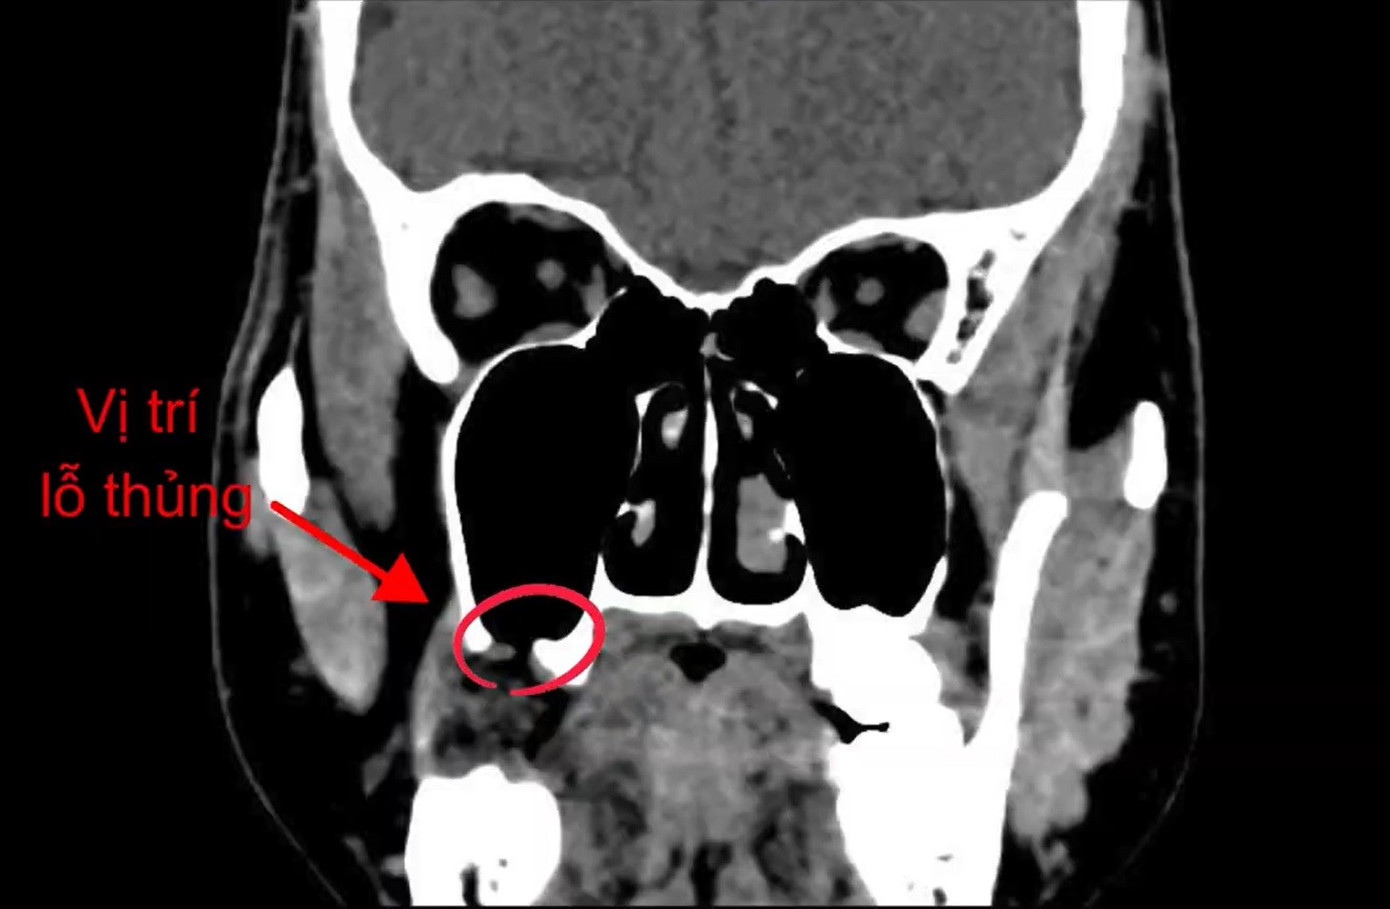

Trên hình ảnh kiểm tra, các bác sĩ phát hiện vị trí xoang hàm của người bệnh bị thủng

BS.Phạm Ngọc Thái Sơn cho biết, kết quả kiểm tra hình ảnh ghi nhận bệnh nhân có lỗ thủng vùng răng số 18 thông vào xoang hàm. Chính lỗ thủng này khiến nước và không khí lưu thông ngược giữa miệng và mũi, gây viêm xoang kéo dài, nghẹt mũi, đau đầu và nặng vùng mặt.